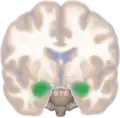

Frontal view of the amygdalae in an average human brain

Amygdala highlighted in green on coronal T1 MRI images